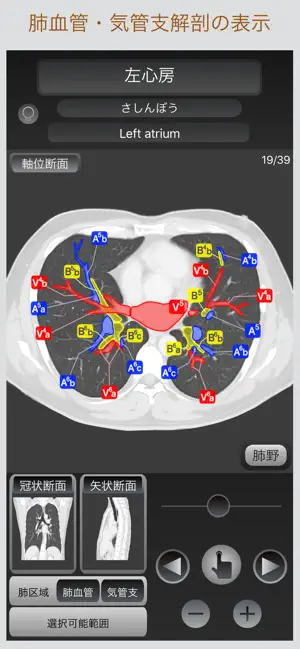

このアプリでは、画像に触れるだけでその解剖名称を表示し、すぐに目的とする箇所を調べられるだけでなく、軸位断面・冠状断面・矢状断面の切り替え表示が可能であり、選択部位の位置関係を瞬時に把握することが出来ます。

■CT画像から解剖名称の選択

画像を指で触れるだけで色分けされた解剖名称を自由に選択する事が出来ます。

■肺区域・肺血管・気管支の表示

肺区域・肺血管・気管支をCT画像上に表示出来ます。